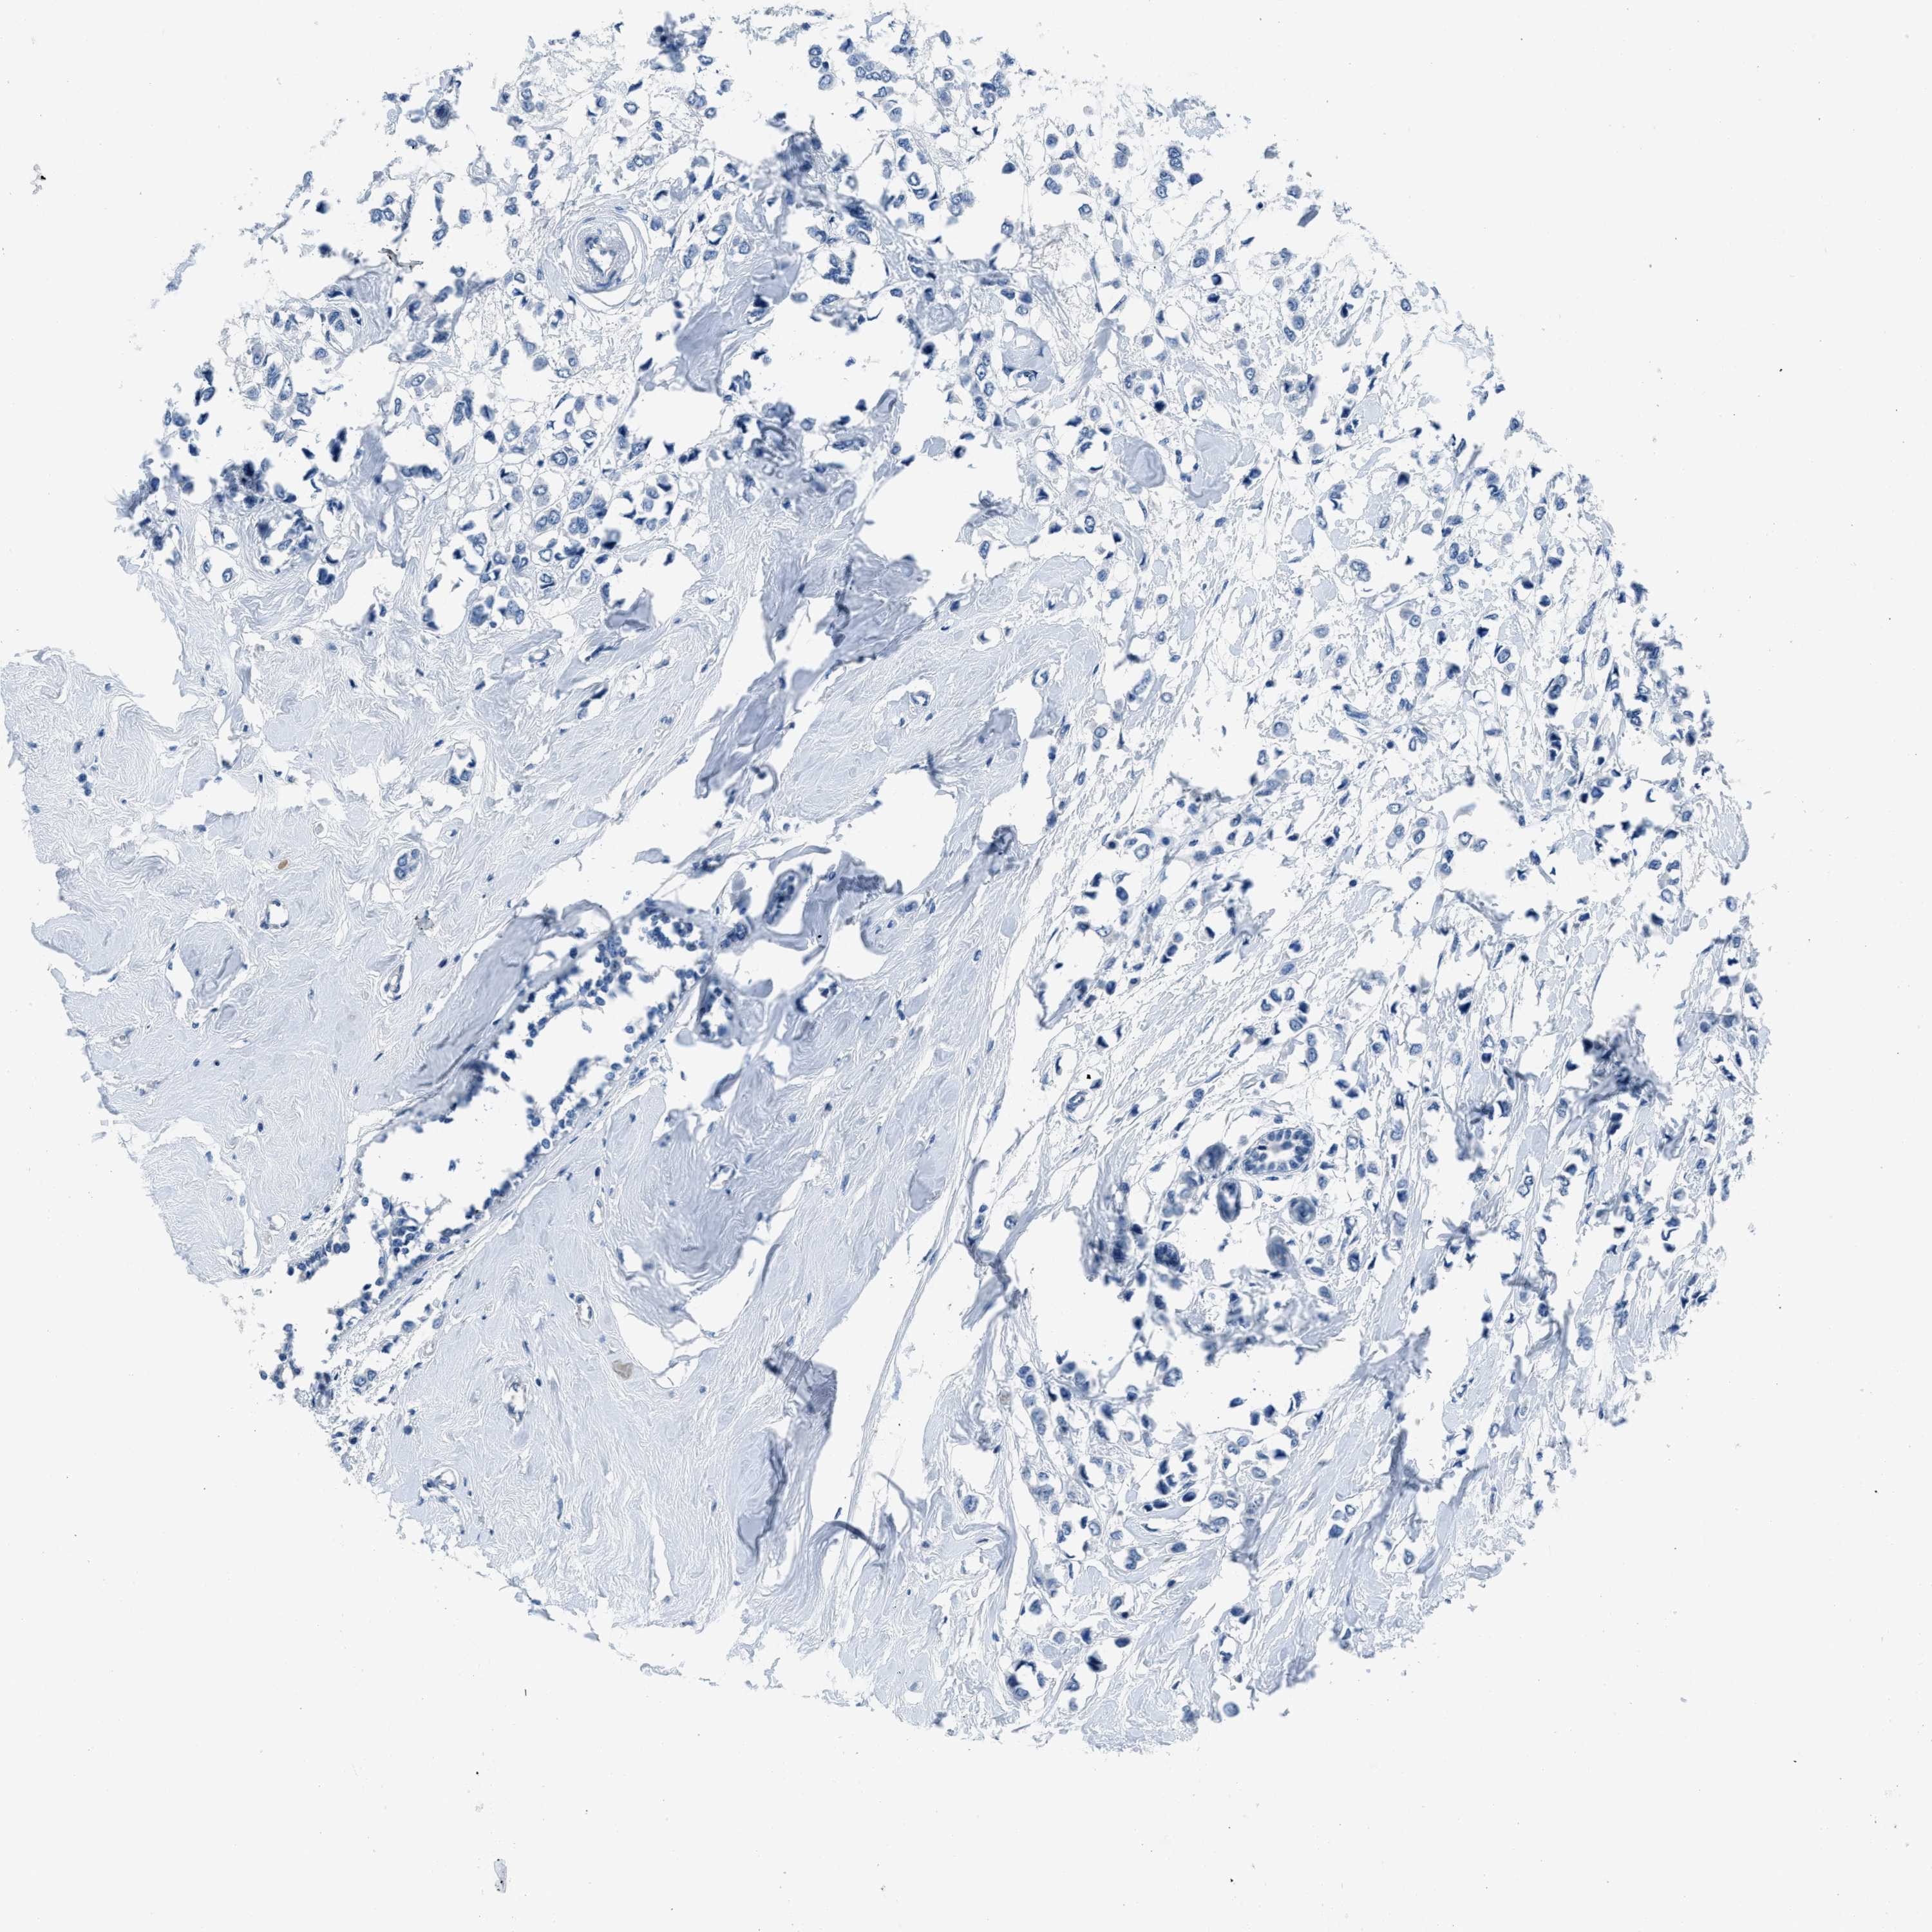

CANCER BREAST CANCER Show tissue menu

Breast cancer

Human cancer

Breast invasive carcinoma